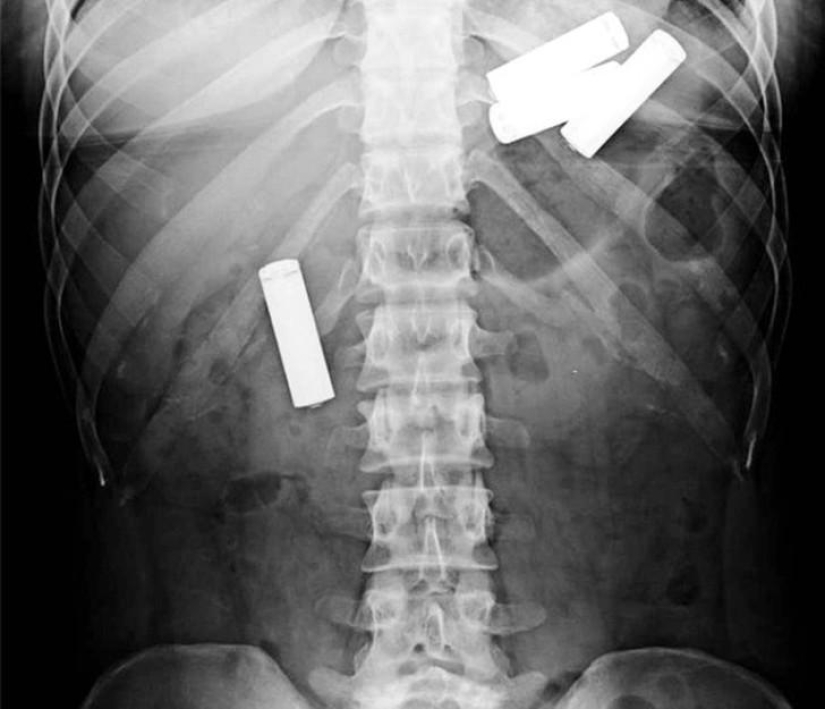

Tijeras.